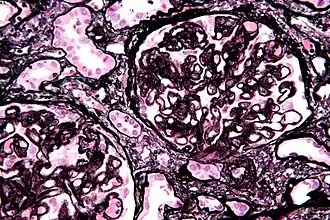

| Histologia da membrana basal glomerular com depósitos de complexos imunes (Tinção de Jones) | |

Histologia

A principal característica microscópica é o espessamento global da membrana basal glomerular com deposição de imunocomplexos nas alças capilares. Atualmente acredita-se que os pacientes portadores de GNM produzam anticorpos contra antígenos presentes nos podócitos ou contra proteínas estranhas ligadas a membrana basal glomerular, levando ao desenvolvimento dessa glomerulopatia.